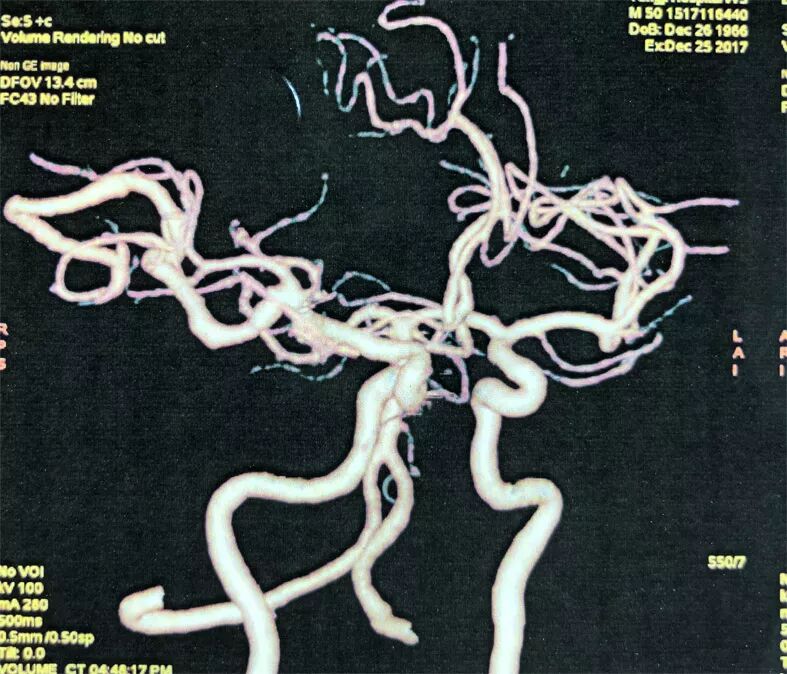

术前影像学检查

2. 术前DSA示:右侧大脑中动脉主供血AVM,向横窦乙状窦引流,合并多发血流相关性动脉瘤。

术后CTA见血管畸形切除完全,IIa动脉瘤夹闭完全